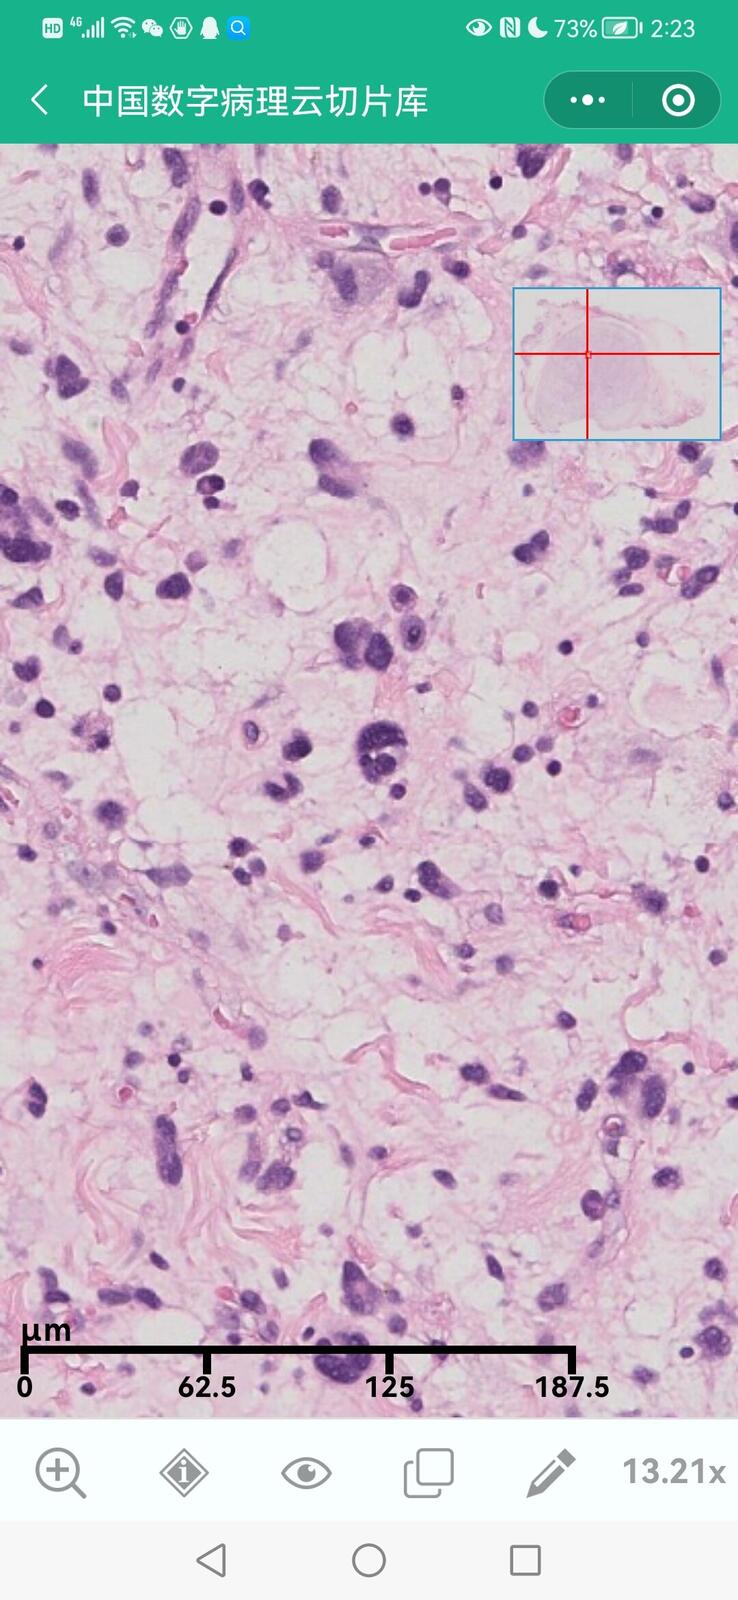

乳腺黏液性囊腺瘤伴导管内癌

乳腺多形性脂肪肉瘤

乳腺叶状囊肉瘤

乳腺分泌性癌(29岁)